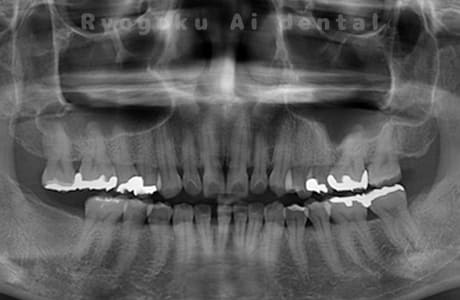

左下からの出血がと違和感があるとのことで転院された患者さんです。衛生士さんとのブラッシング指導、並びに、歯石のお掃除を終えても歯周ポケットの改善がなかったため、再生療法を行いました。歯周ポケットが約8ミリ存在した部分が2ミリに改善し、出血もなくなりました。

<リスク・副作用>

手術後は痛み、腫れ、痺れなどの副作用が生じる場合があります。